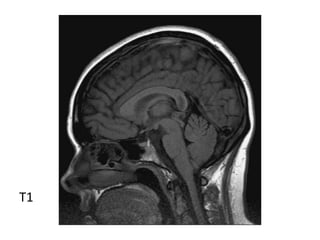

*T1 :

-Typically iso to low signal compared to brain

parenchyma

-55 to 60% are somewhat hyperintense when

compared to CSF

-Generally homogenous signal

T1

T1+C

-Iso to slightly hypointense to grey matter